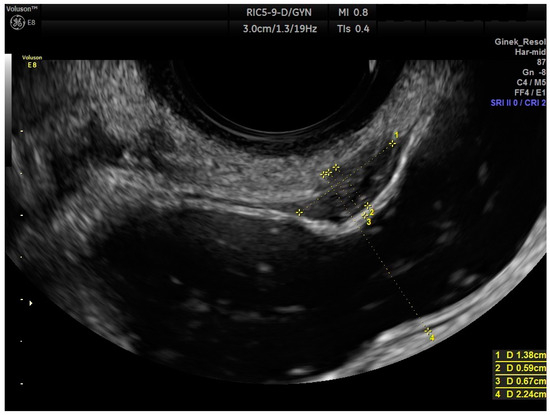

2.2. Ultrasound Measurements